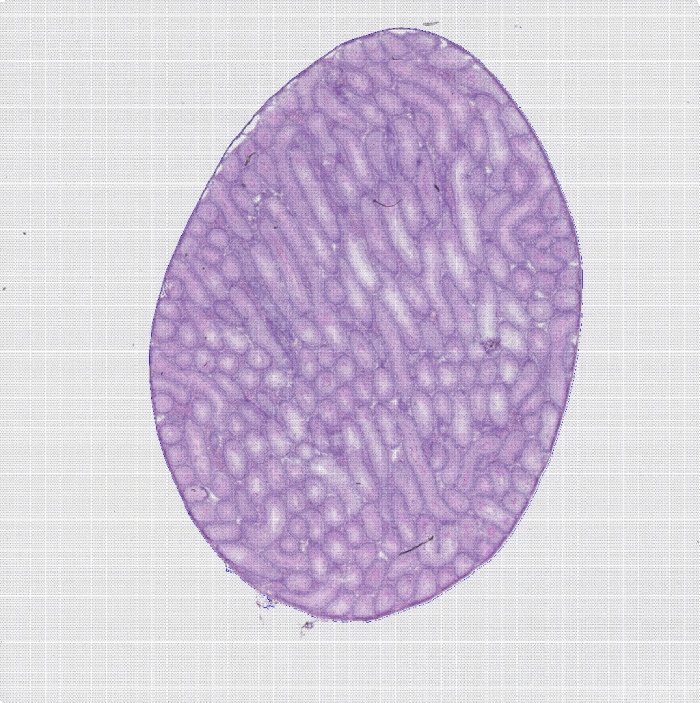

組織切片HE染色圖

圖1 組織切片HE染色圖